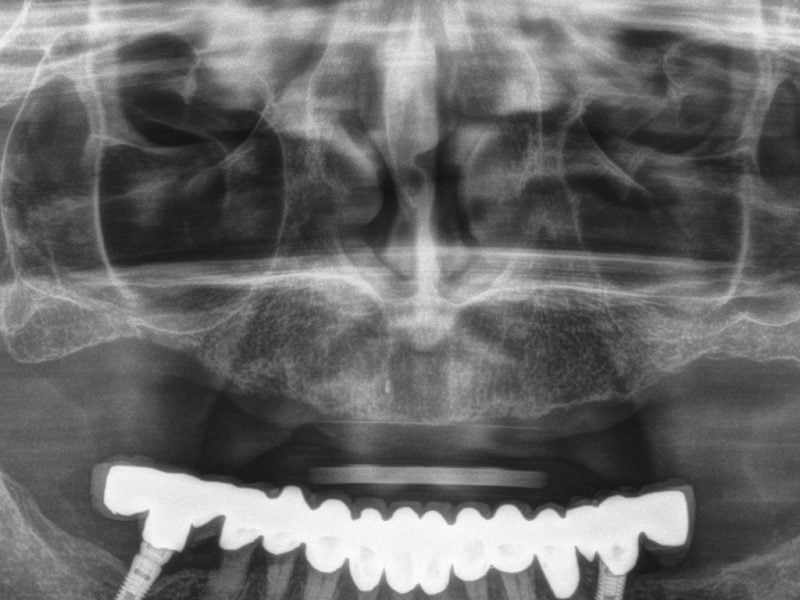

Dr. SHU LING Country: China Gallery Patient’s Data: Age: 59 Sex: Male Smoker: Yes Pathologies: None Hygenic state: Bad Alergies: None The patient has severe periodontitis in the upper jaw, which has no clinical preservation value. Refer to the patient’s CBCT data to design treatment plans which will include the insertion of six B&B implants. […]